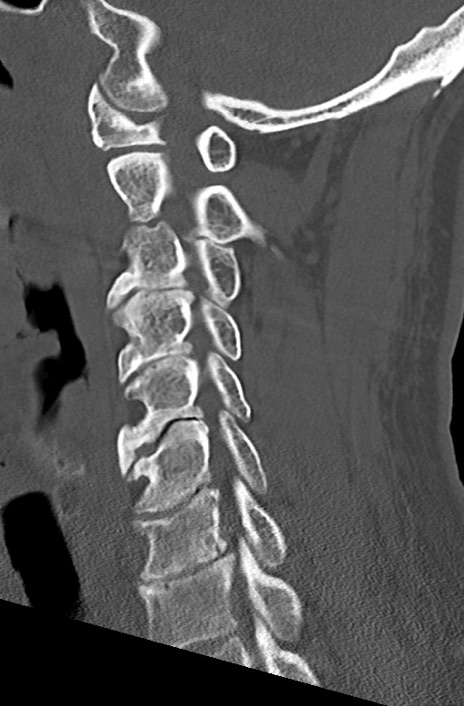

頚椎CT

矢状断像と横断像